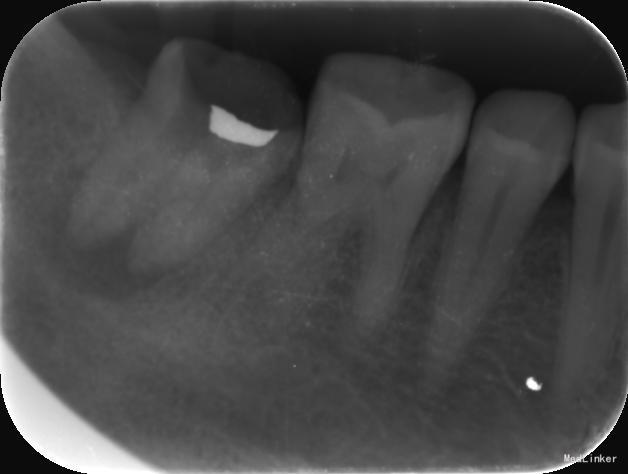

检查:右下7髓腔开放,可见髓腔内食物残渣及部分银汞充填体,叩痛(++), 冷热刺激无反应,松动1度,牙体已制备,牙合龈距离低,X线片示根尖区密度减低区。

诊断:难治性根尖周炎 治疗计划:告知患者病情,治疗难度及预后,拟行根管再治疗,但术后效果不确定,如若不理想拟需行根尖手术甚至牙拔除术。患者知情同意,并要求尽量行保留牙齿治疗。 处置:第一次 揭全髓顶,去腐,疏通根管,测量工作长度,机扩预备至S1,超声荡洗,激光消毒,封CP球。口服抗炎药。一周后复诊。 第二次 复诊无叩痛,暂封物在。去除暂封物,双氧水和盐水交替冲洗,EDTA伴随下根管预备至F2,超声荡洗,激光荡洗+激光消毒,封氢氧化钙。两周后复诊。 第三次 复诊无叩痛,暂封物在。 去除暂封物,双氧水和盐水交替冲洗,EDTA伴随下根管预备至40号,超声荡洗,激光荡洗+激光消毒,封vitapex,玻璃离子体充填。拍X线片。一月后复诊。 第四次 复诊无疼痛 旧充填体在 拍X线片可见根尖阴影变小,故未行任何治疗,嘱患者1月后再次复诊。 第五次 复诊无疼痛 旧充填体在 拍X线片未见根尖阴影变小,故去除旧充填体,冲洗,去除vitpex,根管再次预备,双氧水和盐水交替冲洗,超声荡洗,激光荡洗+激光消毒,封氢氧化钙。两周后复诊。 第六次 复诊无疼痛 去除暂封物,冲洗,见根管内无渗出,试尖,超声荡洗,激光荡洗和消毒,干燥,AHplus糊剂和热牙胶充填,糊剂超填,玻璃离子体充填。请口腔外科医生会诊是否可行根尖手术,外科医生建议因手术难度大,且病变与下颌神经管接近,建议随诊观察,暂不考虑行根尖手术。必要时考虑意向性牙再植术或者牙拔除术。嘱患者1月后复诊,结果患者失诊。